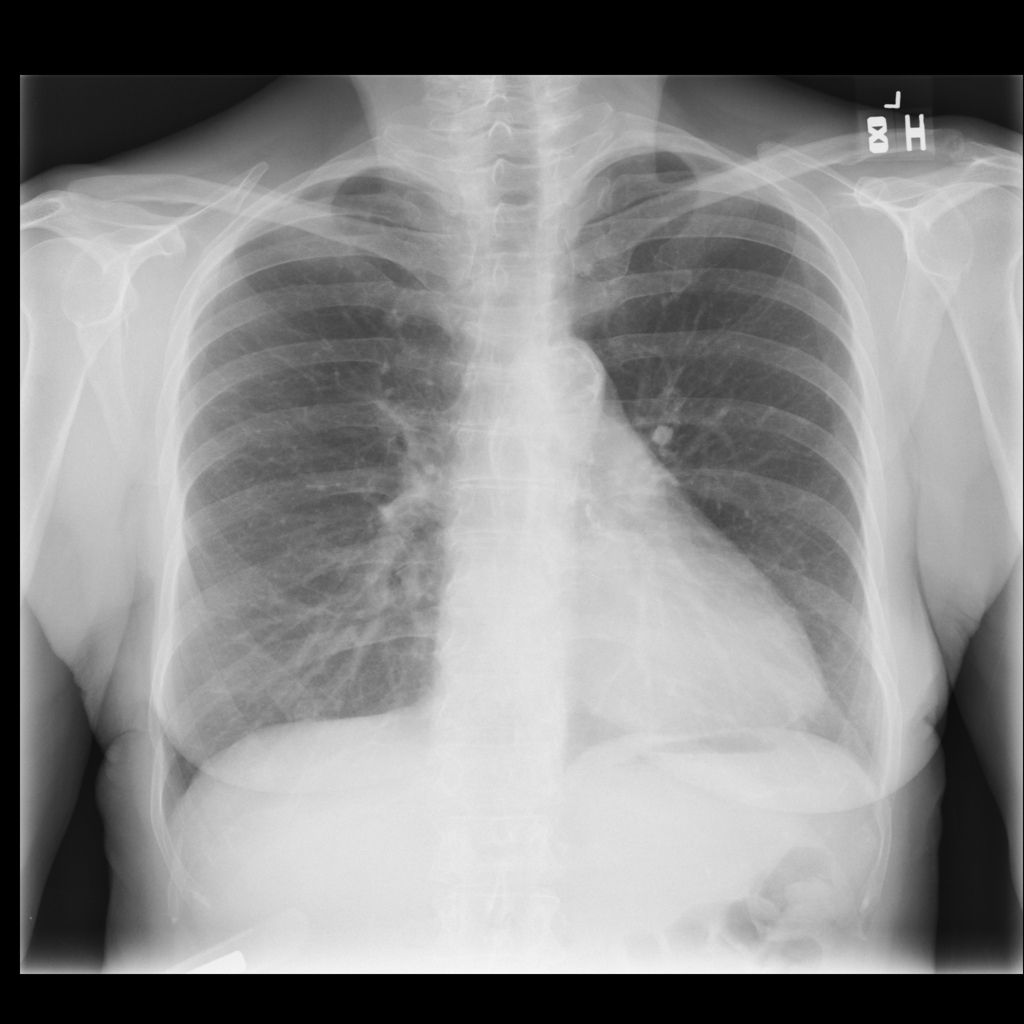

Showing up to 90 reference images for Nodule.

PAT-250B · IMG-000Nodule

PAT-250B · IMG-000

PA